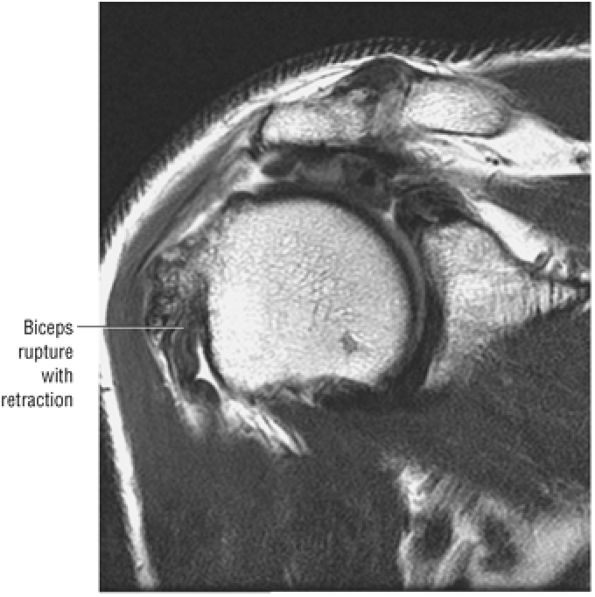

stripped from its lesser tuberosity attachment. However, because of an intact connection with the transverse humeral ligament, which connects the subscapularis tendon to the greater tuberosity, the tendon fibers appear to course in continuity without retraction. Proximal biceps tendon and subscapularis tendon pathology commonly coexist, since the pathogenesis of tendinosis and tears of both tendons are interrelated.